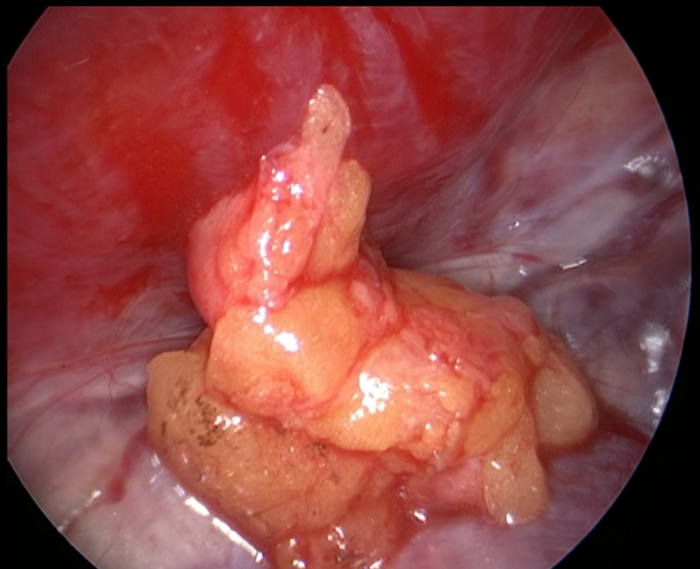

再以皮下切口周围脂肪组织分块、阶梯式妥善填塞漏口周围和整个囊腔(如下图示)